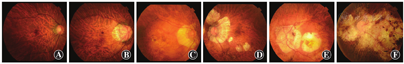

近视性黄斑病变,又称近视性黄斑变性,是病理性近视的重要特征。Curtin和Karlin[70]最先描述了5种与眼轴增长相关的近视性眼底改变,包括视盘萎缩弧、脉络膜视网膜萎缩、中央区色素紊乱、漆裂纹和后巩膜葡萄肿。后来,Avila等[108]研发了近视性黄斑病变的分级系统,其严重程度从0~5递增:M0为后极部外观正常;M1为脉络膜颜色变淡和豹纹状改变;M2为M1+后巩膜葡萄肿;M3为M2+漆裂纹;M4为M3+深层脉络膜萎缩病灶;M5为大面积的深层脉络膜视网膜萎缩,表现为"巩膜暴露"。在病理性近视的图集中[109],Tokoro更新和编辑了近视性黄斑病变的病变特征。Tokoro[109]根据检眼镜眼底检查结果将近视性黄斑病变分为4类:(1)豹纹状眼底;(2)弥漫性脉络膜萎缩;(3)局限性脉络膜萎缩;(4)黄斑出血。漆裂纹为弥漫性萎缩型,黄斑出血分为近视性MNV和单纯性黄斑出血2个亚型。随后,Hayashi等[98]对429例高度近视(近视性屈光不正>8 D或眼轴长度≥26.5 mm)患者806眼的自然病程进行了调查,随访5~32年。基于临床表现对Tokoro的分类进行了一些修订,将漆裂纹和近视性MNV归类为独立病变。这种对所有近视性黄斑病变损害的纵向观察为随后通用分类法(META-PM分类)的制定做出了巨大贡献[3]。

最近,一个国际近视研究小组回顾了既往的研究,并提出了一种简化的、统一的病理性近视分类系统(表2)。在这个简化的系统(META-PM分类法)中,近视性黄斑病变的损害分为5类,分别为无近视性视网膜病变(第0类)、仅豹纹状眼底改变(第1类)、弥漫性脉络膜视网膜萎缩(第2类)、局限性脉络膜视网膜萎缩(第3类)和黄斑萎缩(第4类)。在这个分类中增加了3个"附加体征":(1)漆裂纹;(2)近视性MNV;(3)Fuchs斑。将这些附加体征从分类中分开是因为这3种附加体征影响或潜在影响中心视力,可能由任何类别的近视性黄斑病变产生或共存。基于这种分类,病理性近视被定义为等于或大于第2类近视性黄斑病变,或存在附加体征、后巩膜葡萄肿。

豹纹状眼底的定义是由于眼轴增长导致脉络膜大血管可见性增加(图9)。豹纹状改变最先发展在视盘周围,特别是在视盘和中央凹之间的区域。与近视性黄斑病变的其他病变不同,单独的豹纹状眼底不影响中心视力(表2)。豹纹状眼底和近视弧是近视初期可见的征象之一,常见于高度近视儿童[110]。Wong等[111]也报道了在高度近视的中国青少年(12~16岁)中,最常见的是豹纹状眼底和视盘周围萎缩。

弥漫性脉络膜萎缩是出现在高度近视眼后极部眼底的一种边界不清的黄色病灶。病灶呈不均一黄色,颗粒状外观。然而,不同种族的眼底色素沉着程度不同,眼底颜色也可能不同。弥漫性脉络膜萎缩主要出现在视盘周围,并随着年龄的增长而增加,最终覆盖整个后极部[109]。因此,弥漫性脉络膜萎缩可分为乳头周围弥漫性脉络膜萎缩(peripapillary diffuse choroidal atrophy,PDCA)[30]和黄斑区弥漫性脉络膜萎缩(macular diffuse choroidal atrophy,MDCA)[77]2个亚型。弥漫性萎缩的发生率随年龄和眼轴长度的增长而增加[28,115]。Tokoro等[115]发现弥漫性萎缩通常发生在40岁左右,30%~40%的患者在40岁后出现。最近,Liu等[28]采用META-PM分类法,从年龄、眼轴长度和最佳矫正视力方面对弥漫性脉络膜萎缩的频率和分布进行评估。在中国的大规模高度近视人群中,7~11、12~18、19~39和40岁以上人群弥漫性脉络膜萎缩的比例分别为20.9%、9.2%、23.1%和52.9%。弥漫性脉络膜萎缩的发生率随着眼轴长度的增长而增加,眼轴长度<26.50 mm的患者发生率为3.6%,眼轴长度≥28.50 mm的患者发生率为62.8%。

局限性脉络膜萎缩是一种灰白色、界限清晰的萎缩[109]。由于RPE和大部分脉络膜的缺失,可以通过透明的视网膜组织观察到巩膜。局限性萎缩面积为0.03~101.3 mm2,平均1.73 mm2[117],直径<1个或多个脉络膜毛细血管小叶。在局限性萎缩区域内,特别是沿着萎缩的边缘或脉络膜大血管,可以观察到色素块[118]。在局限性萎缩的内部或边缘附近,通常可以观察到突然出现的血管,尤其是那些大的萎缩灶中[118]。临床上,日本的高度近视人群中10.5%的患者出现局限性萎缩[117]。局限性萎缩的百分比随年龄增长呈线性增加,60岁后达到32.5%[115]。眼轴长度为27.0~27.9 mm的眼局限性萎缩的患病率为3.3%,如果眼轴长度超过31 mm和32 mm,局限性萎缩的患病率分别超过25%和50%[115]。随着时间的推移,局限性萎缩扩大并相互合并[77,98,119]。

黄斑萎缩是以中央凹为中心,一种边界清楚、灰白色或白色的萎缩性病变。影像学特征与局限性脉络膜视网膜萎缩相似。局限性萎缩和黄斑萎缩的主要区别在于其位置相对接近中央凹。根据长期随访观察,黄斑萎缩可分为MNV相关的黄斑萎缩和局限性萎缩相关的黄斑萎缩。MNV相关的黄斑萎缩以中央凹为中心并向周围扩大,局限性萎缩相关的黄斑萎缩在中央凹区域以外发展并扩大,或与其他局限性萎缩合并进入中央凹[77]。这种划分方法主要是基于形态特征或MNV病史。大部分黄斑萎缩是MNV的萎缩阶段,少数与局限性萎缩扩大继发性累及中央凹有关。

在黄斑区内和周围可以观察到细的、不规则的黄色线状漆裂纹。漆裂纹被认为是RPE、Bruch膜和脉络膜毛细血管复合体的愈合和机械断裂[67,68]。多条漆裂纹常呈分枝状或交叉状。在多项队列研究中,高度近视眼漆裂纹的患病率为4.2%~15.7%[27,67,68,69,124]。在病理性近视患者中,漆裂纹可以在较早的年龄发生。Klein和Curtin[68]报道漆裂纹患者的年龄为14~52岁,平均32岁。之前的研究也表明,漆裂纹多发于眼轴长度为29.0~32.0 mm的眼[27,67,68,69,71,124,125,126,127]。

MNV是病理性近视中心视力受损的主要原因,其已作为附加体征包含在META-PM分类中。MNV分为3个阶段:以MNV、渗出和出血在内的纤维血管膜增生为表现的活跃期;以Fuchs斑为表现的瘢痕期;以MNV相关性黄斑萎缩为代表的萎缩期。因此,Fuchs斑不被认为是独立的病变,其是MNV瘢痕期的表现。更多的细节将在"近视性MNV"一节中讨论。